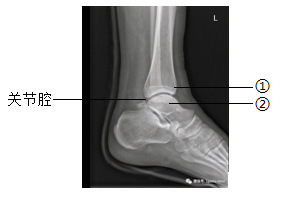

16. 下图为某人左脚的踝关节射线透视图像,①②表示踝关节内的结构。下列说法错误的是( )

A. ①是关节头,②是关节窝

B. ①②表面覆盖着关节软骨

C. 关节腔内有滑液,使关节灵活

D. 踝关节在运动中起枢纽(支点)作用